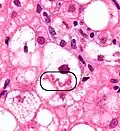

NASH (inflammation) and fibrosis stage 1 -

Two foci of lobular inflammation.